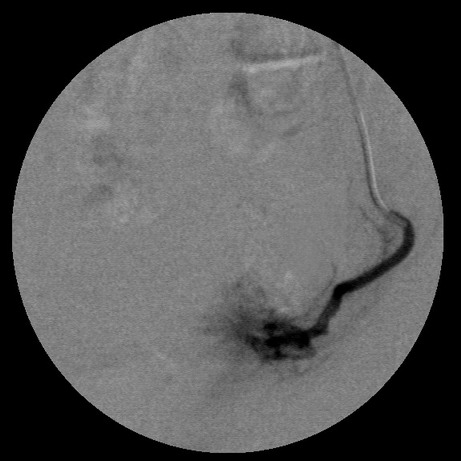

女,35岁,子宫多发肌瘤

栓塞剂用的是进口pva,二瓶,几千块呀,栓塞面积应该不大吧,呵呵

要超选到子宫动脉上支吗?